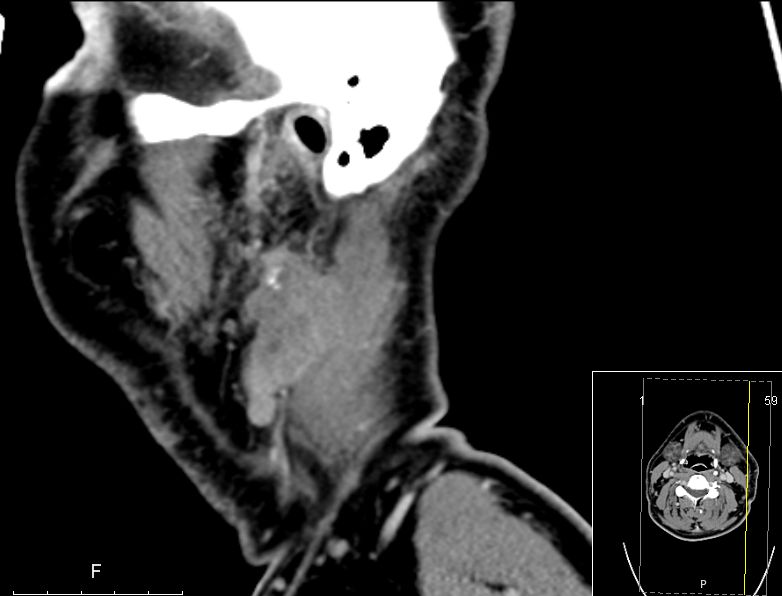

| CT | 51-jähriger Mann, der eine Gesichtsschwellung bemerkte. Adenokarzinom pT3 pN1 Mo L1 G3. Subtotale Protidektomie unter Neuromonitoring, ND LI und II links, Adjuvante RT. ![]() |